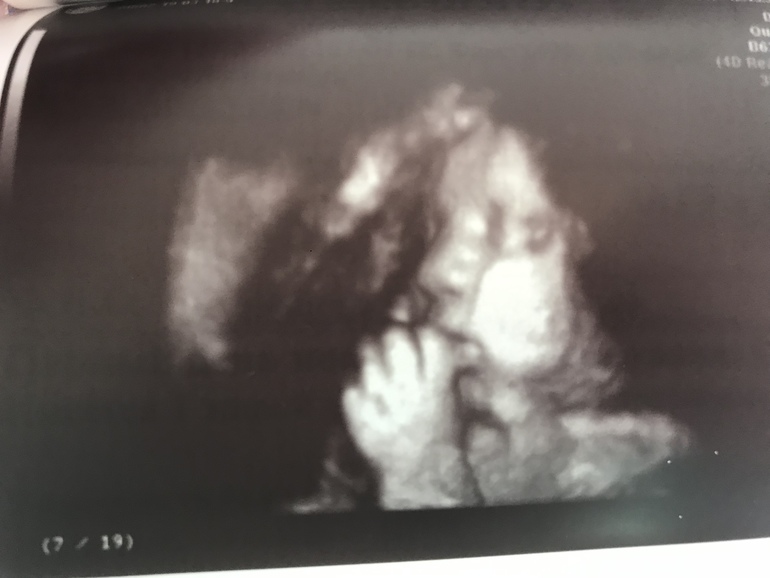

Вес 1901гр😍

Он много раз сказал, что это папина дочка (ресницы длинные, губы пухлые, головка большая)❤️ А волосы в маму «будет светлая шатенка, волосы кудрявенькие»😁

Пальчик сосала, потом губы трубочкой сложила, а он говорит «она плюётся!🤦🏻♀️😁 кто у тебя из сыновей ещё плюётся?». Я так подумала и отвечаю «средний», а он «так у тебя дети через одного плюются!»🙈😂

Спросил, как назвала. Я ответила «Арина», а он «не Родионовна?», я «нет, Валентиновна» - и она в этот момент улыбнулась 😊😍

Всё УЗИ была серьёзная, а тут улыбнулась... Моя принцесса 👑, моё солнышко ❤️